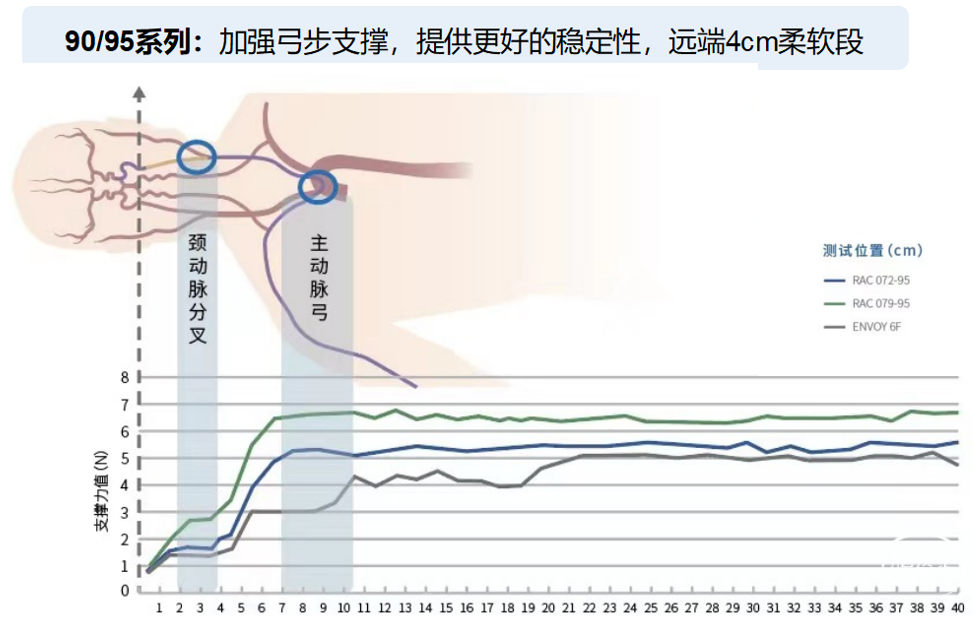

赛诺经桡通路系列产品

桡动脉通路导引系统产品介绍

针对不同规格,更合理的分段设计:

注:*为多个病例证实,但由于公差、血管迂曲等因素,可能存在阻力较大等情况。